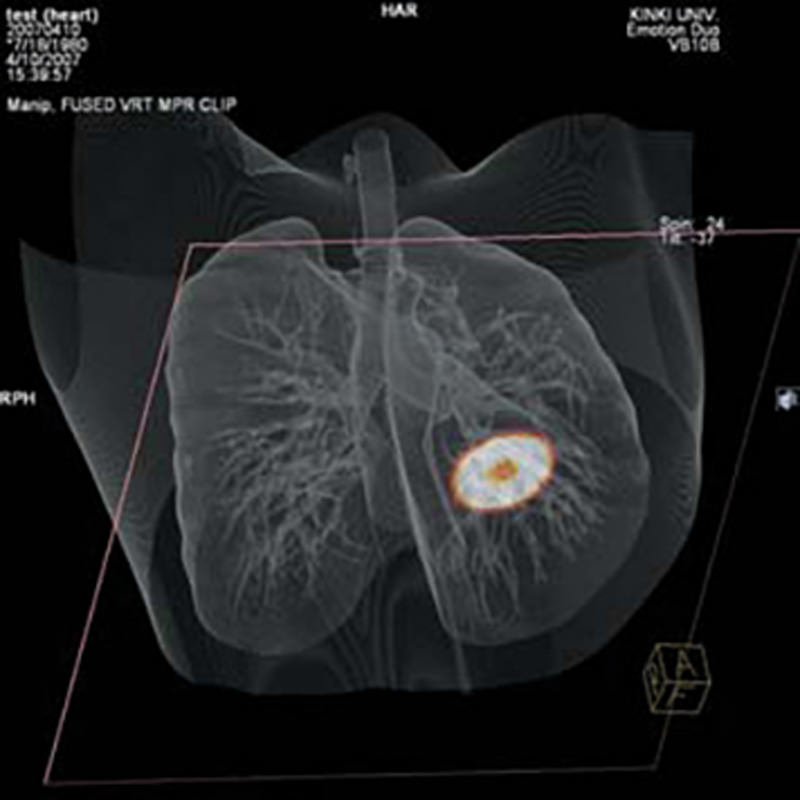

Dieses Vielzweck-Übungsmodell eignet sich für Aufnahmen mit Röntgengeräten und mit Computertomographen. Es eignet sich sowohl zum Erlernen der Aufnahmetechnik als auch für die Ausbildung der Bildinterpretation. Auch für die Gerätewartung und –einstellung eignet sich dieses Modell hervorragend. Die Strukturen des Modells sind aus Materialien mit annähernd natürlichen Röntgenabsorptionswerten gefertigt. Das Model kann geöffnet werden und künstliche Tumore können in die Lunge eingebracht werden. 15 unterschiedliche Tumore werden mitgeliefert.